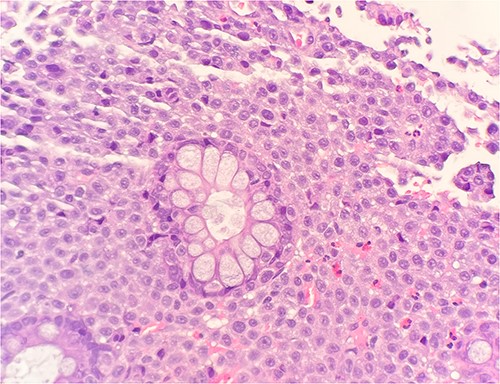

Immunohistochemical stains demonstrate the tumor cells to be strongly positive for vimentin, pankeratin, CK7, CK20, chromogranin, synaptophysin, CD45, and focally positive for CD56. Additionally, there were strongly and diffusely positive findings for S100 (Fig. 3), SOX10, and PRAME. Ki67 shows increased proliferative activity at estimated 25–30%. CD99 shows weak and patchy membranous staining while CK-PAN, p63, desmin, and smooth muscle actin are negative. The described morphology and immunoprofile are consistent with malignant melanoma.

Microscopic examination reveals sheets of round are positive for S100. IHC stain 40×.